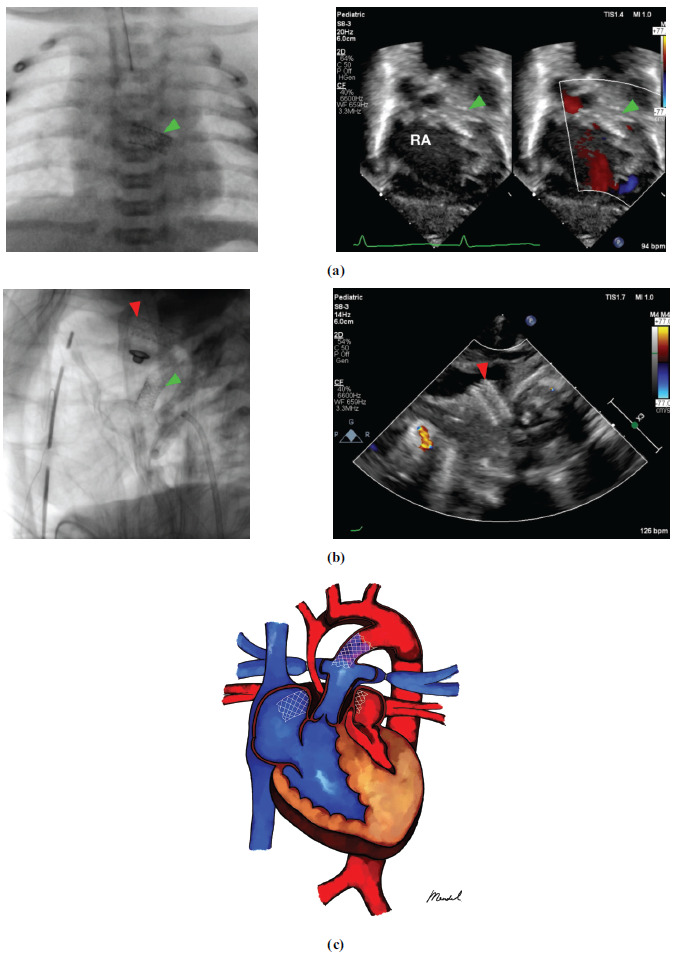

Background: Inter-atrial septum (IAS) stenting in duct-dependent congenital heart disease patient has shown to be an effective way to maintain inter-atrial blood flow, however it is still considered a high risk procedure and inter-atrial septum stenting remains a low-frequency procedure.

Method: A single-center observational cohort study was carried out at the National Cardiovascular Center Harapan Kita (NCCHK) between April 2019 and April 2023. This study included duct-dependent congenital heart disease patients. The extracted data were baseline characteristics, clinical findings, complications, and outcomes of the patients.

Result: Eleven patients with duct-dependent physiology were intervened with inter-atrial septum stenting. The patients were 4 females and 7 males with the median age of implantation being 150 days (range 11-703 days) and the median weight being 3.9 (range 2.8-9) kg, with 2 patients weighing less than 3 kg. The average stent diameter was 8.50 (2.03) mm with an average length of 24.45 (7.94) mm. Non-restrictive atrial flow was successfully achieved in 90.90% of the procedures, corresponding to 10 patients.

Conclusion: Inter-atrial septum stenting in duct-dependent congenital heart disease patients produces reliable patency with a very good intra-procedural success rate.